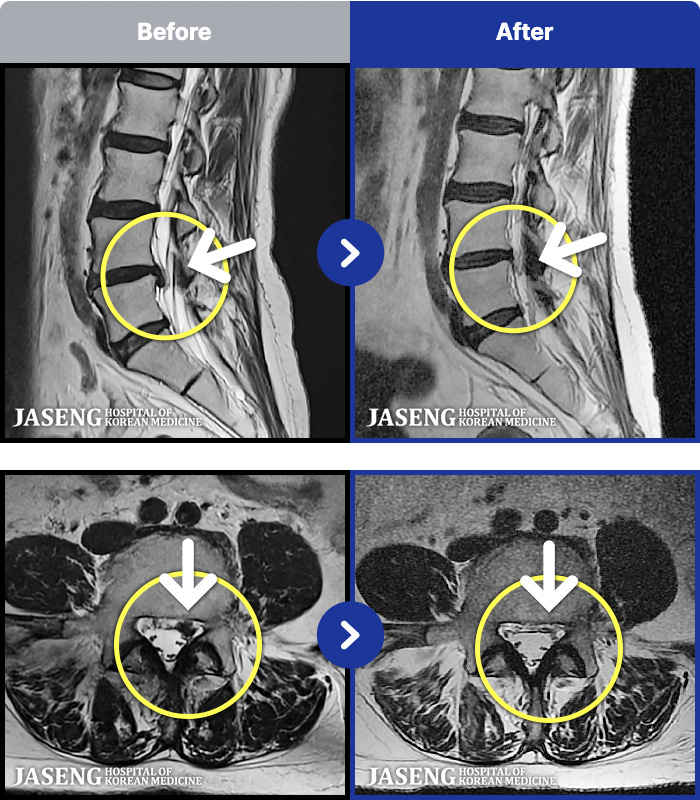

[Կñ:25.03.29~25.07.17]

[_㸮ũ] 㸮

No.52

ȸ 59